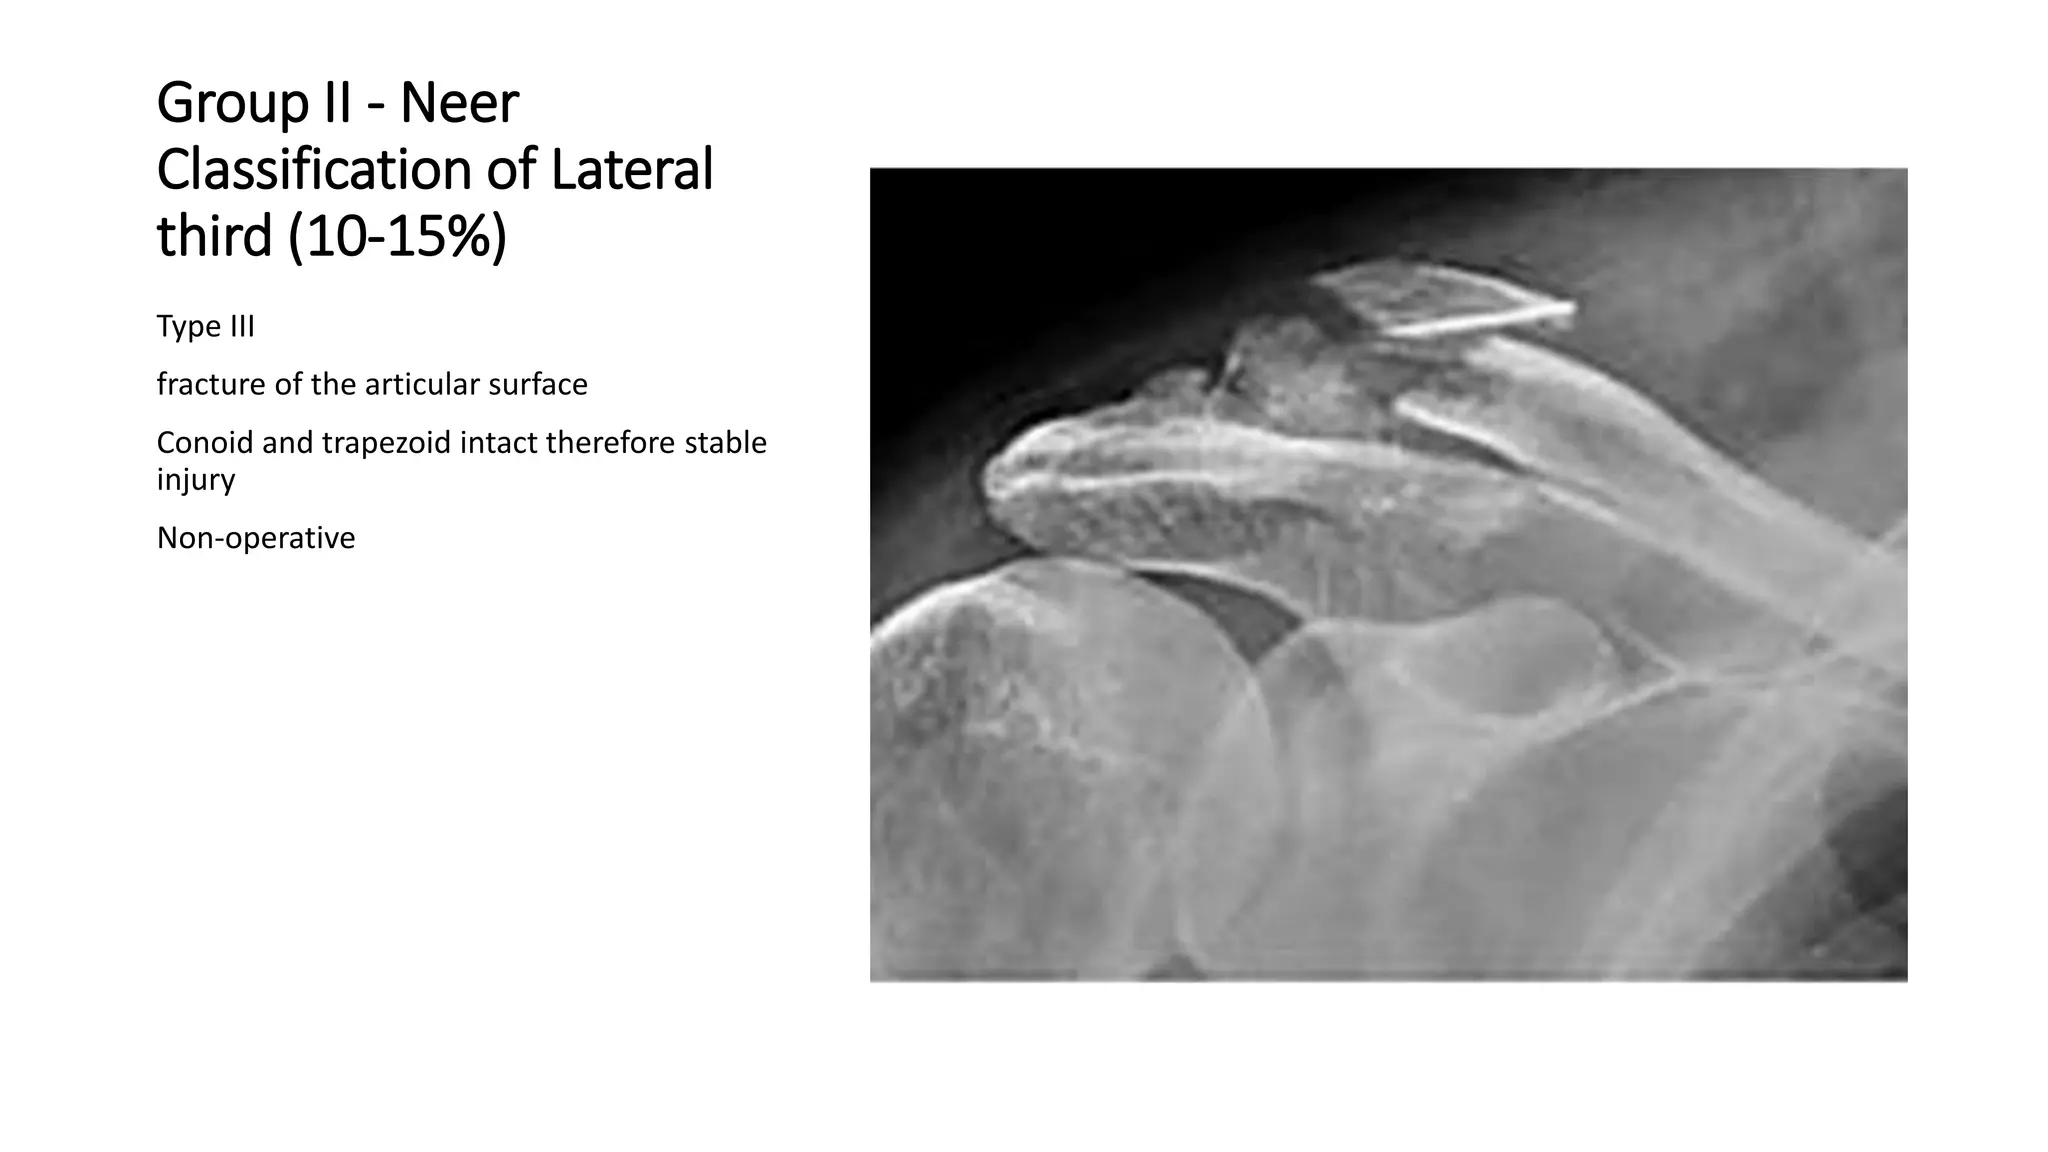

Group II - Neer

Classification of Lateral

third (10-15%)

Type III

fracture of the articular surface

Conoid and trapezoid intact therefore stable

injury

Non-operative